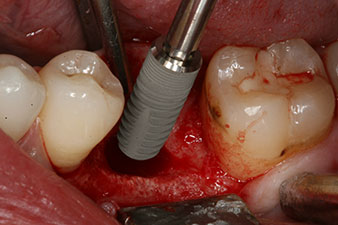

No obstante, seis semanas después de la extracción, tras la disección del colgajo mucoperióstico, se observó una osificación incompleta en el área del antiguo alvéolo mesial.

Tras la extirpación minuciosa del tejido de granulación, se incorporó el implante tal como se había planificado (blueSky, bredent).

El torque en el momento de la carga mecánica fue de 43 Ncm. Asimismo, después de atornillar un poste de medición especial adaptado al sistema de implante (SmartPeg), el valor ISQ se determinó con la sonda del módulo Osstell ISQ de W&H.

Este módulo Osstell ISQ que se encuentra disponible como accesorio para la unidad Implantmed de W&H y se acopla al motor de implantes (véase figura 11). El valor ISQ adimensional fue de 64 justo en el momento de la inserción en la dirección bucovestibular y de 68 en la dirección mesiodistal (valor máximo = 100).